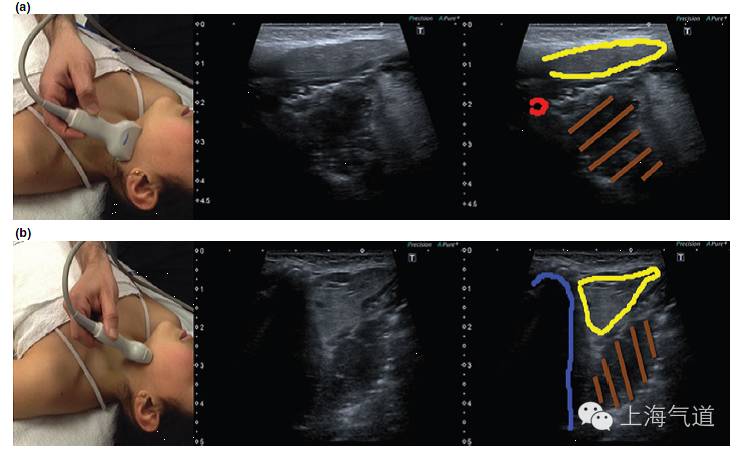

图4a. 假声带水平横截面显示,黄色为带状肌,蓝色为甲状软骨,橙色为假声带。b.将探头轻微向尾端移动至真声带水平,蓝色为甲状软骨,橙色为真声带,红色为前联合,黄色为杓状软骨